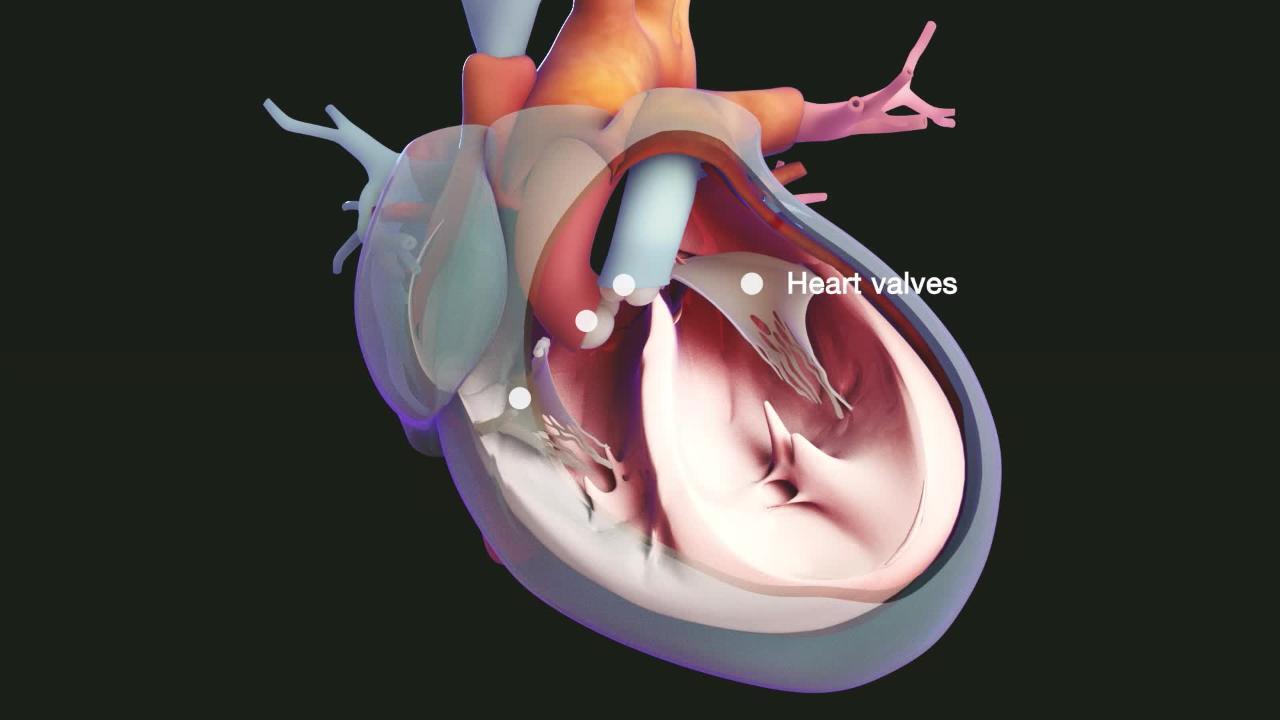

Фотографии и информация о приобретенных пороках сердца